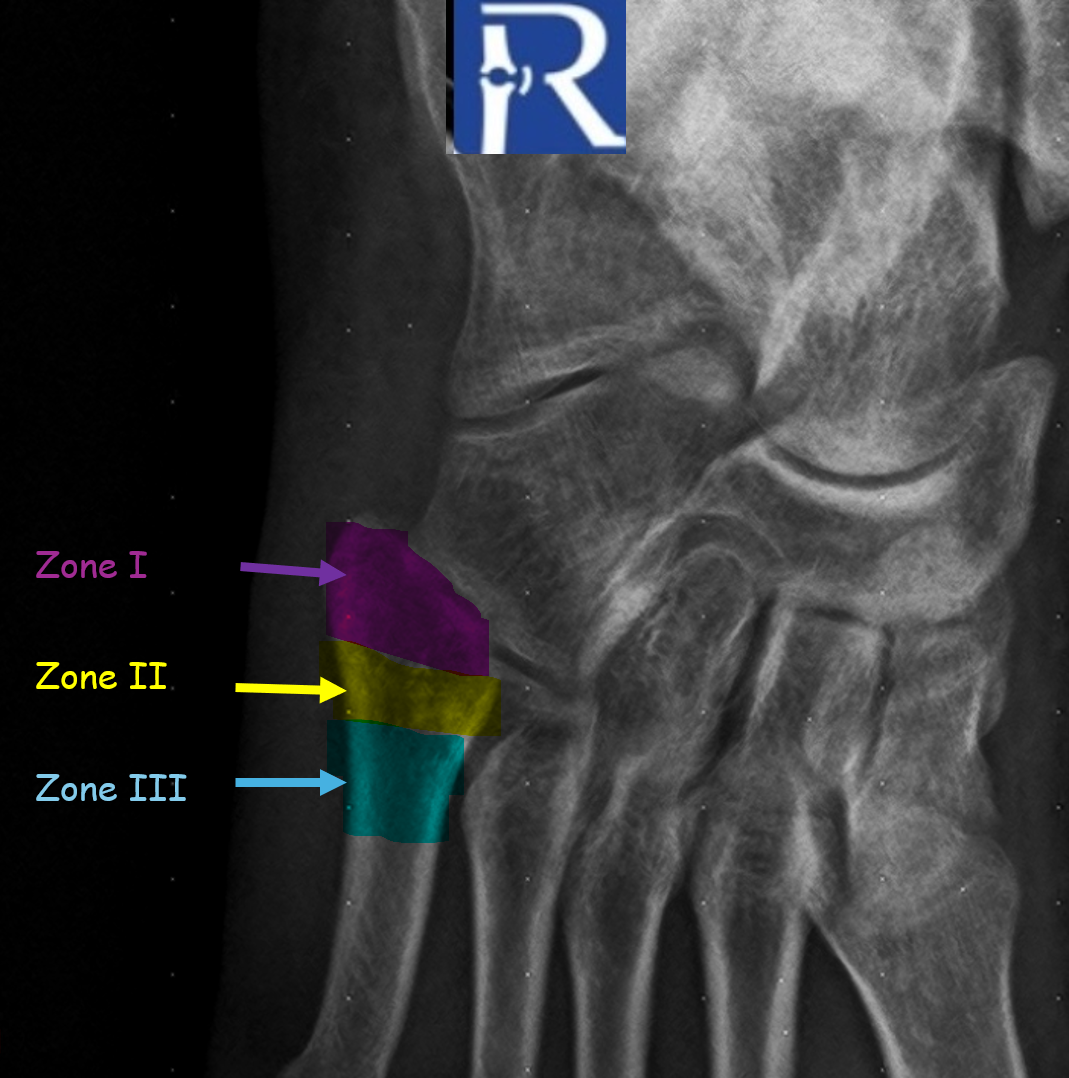

Case Presentation Plantar vein thrombosis (PVT) has traditionally been described as a rare cause of foot pain. However, increasing awareness and mo ...